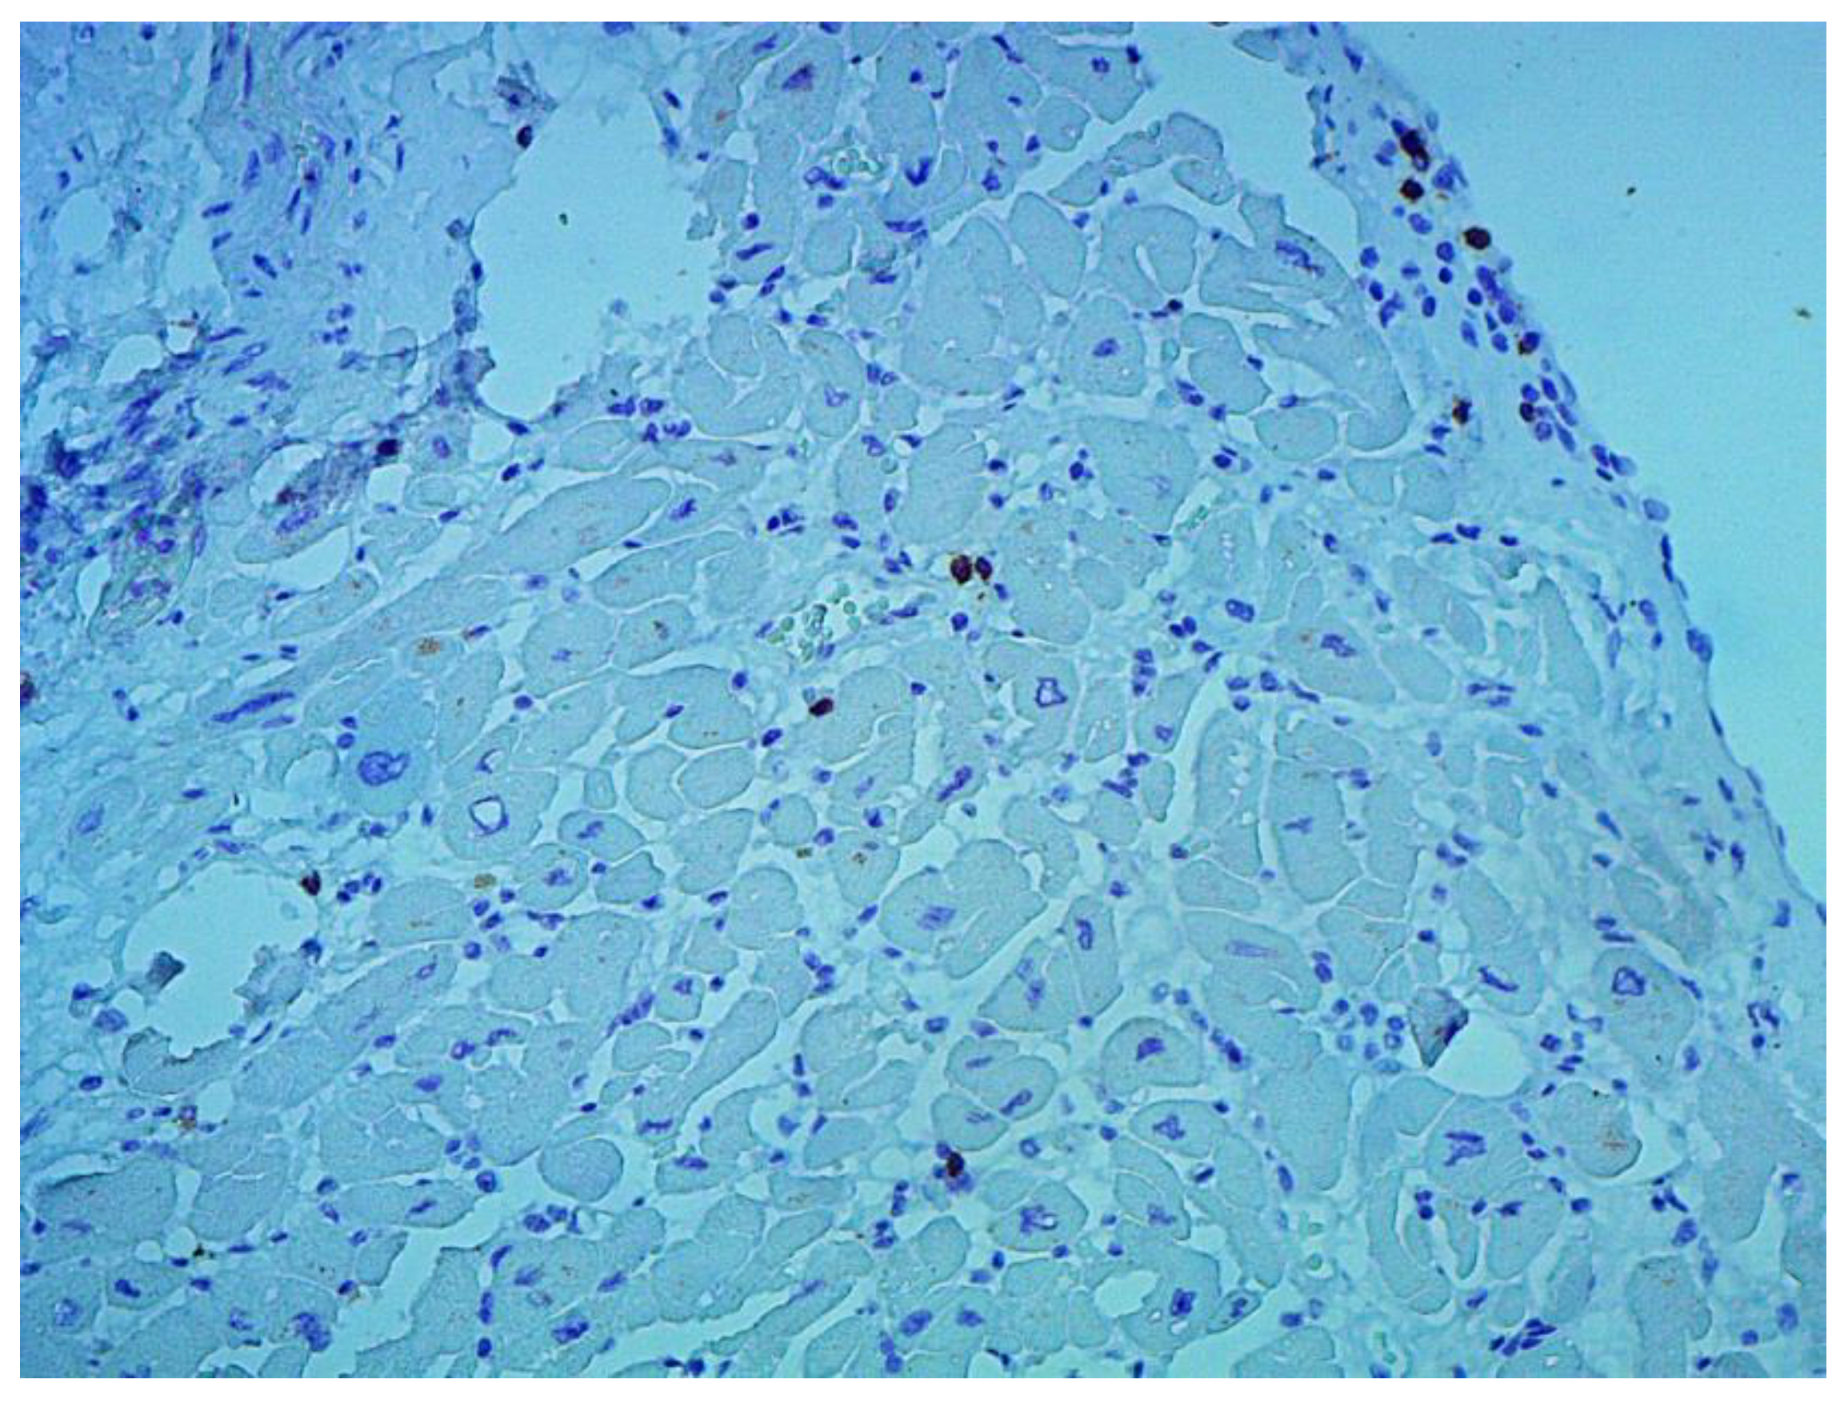

Figure 7. Expression of the enterovirus antigen VP1 in the myocardium. Immunohistochemical study, monoclonal mouse antibodies, ×400.

According to the Dallas criteria, the presence of histological myocarditis was revealed in 23 patients (34.3%) (Figure 6). Moreover, the virus expression was detected in 18 of these patients (78.3%), according to the results of immunohistochemical analysis. One patient (5.6%) was found to express three viruses: enterovirus, human herpes simplex virus type 1, and Epstein-Barr virus; six patients (33.3%) had the presence of two viruses: one patient had a combination of parvovirus and herpes simplex virus type 2; three patients had a combination of enterovirus and herpes simplex virus type 1; and two patients had a combination of Epstein-Barr virus and human herpes simplex virus type 2. The presence of one viral antigen was detected in 11 cases (61.1%), including five patients (27.8%) with Epstein-Barr virus, three patients (16.7%) with enterovirus (Figure 7), two patients (11.1%) with human herpes simplex virus, and one patient (5.6%) with parvovirus. Another five patients (21.7%) did not have viral infection.